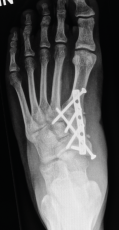

Röntgenbilder

Für die OP-Planung sind auch detaillierte Röntgenbilder unerlässlich. Sie dokumentieren die Fußknochen und den Grad der Fehlstellung aus verschiedenen Blickwinkeln. Am linken Fuß ist die Abweichung des Längsgewölbes und die Verschiebung der Knochen deutlich erkennbar.

Röntgenkontrolle

Die Kontrollaufnahmen unmittelbar nach dem Eingriff zeigen die anatomisch korrigierte Fußform. Die eingebrachten Schrauben stützen den Aufbau so lange bis der Knochen vollständig verheilt ist.